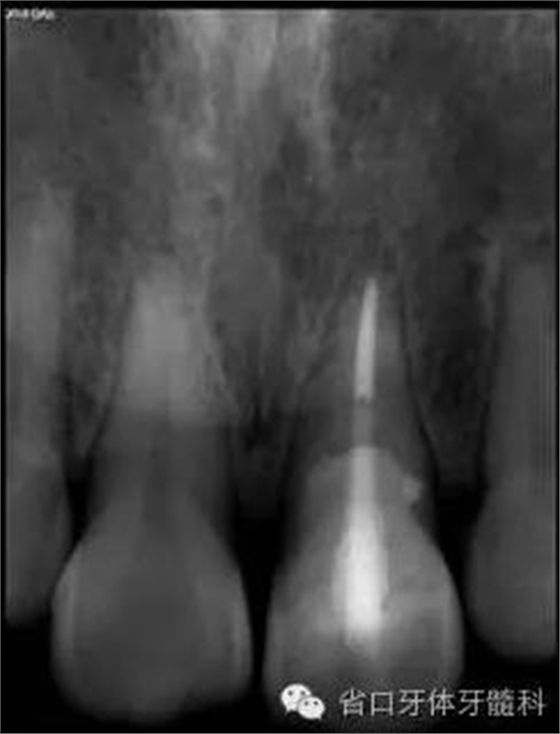

圖8. 21/行根管治療術(shù),保留根尖約5mm的根充物,根中上段預(yù)留空間以預(yù)備纖維樁道。

圖17. 術(shù)后X線片